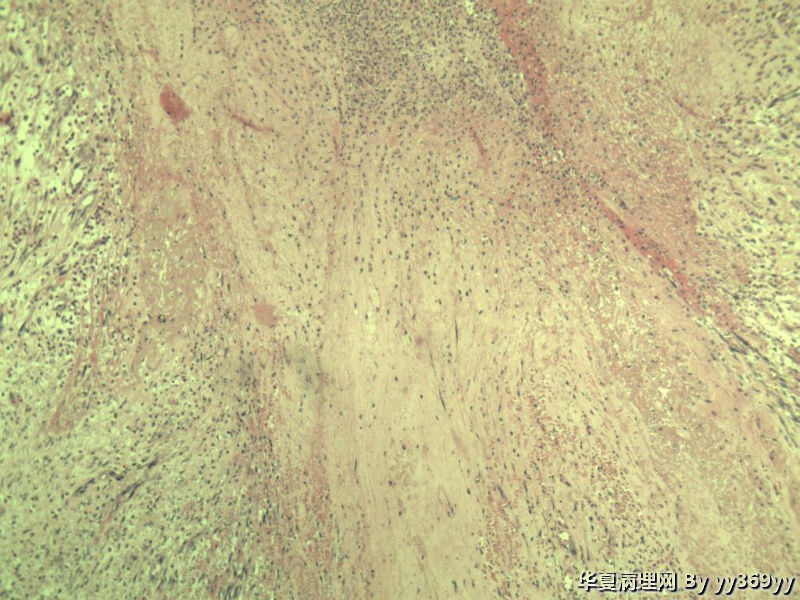

男 30岁 小肠一段,肠管严重粘连可见一体积为 2.5 × 2 × 1.5 cm3的肿块,切面灰白,实性,质中

肿块确切位置?图片颜色不正,需要考虑的有:脂肪坏死/腹腔纤维瘤病/炎性肌纤维母细胞瘤等。

也可能是反应性病变。

纤维瘤病?

还有GIST需要鉴别